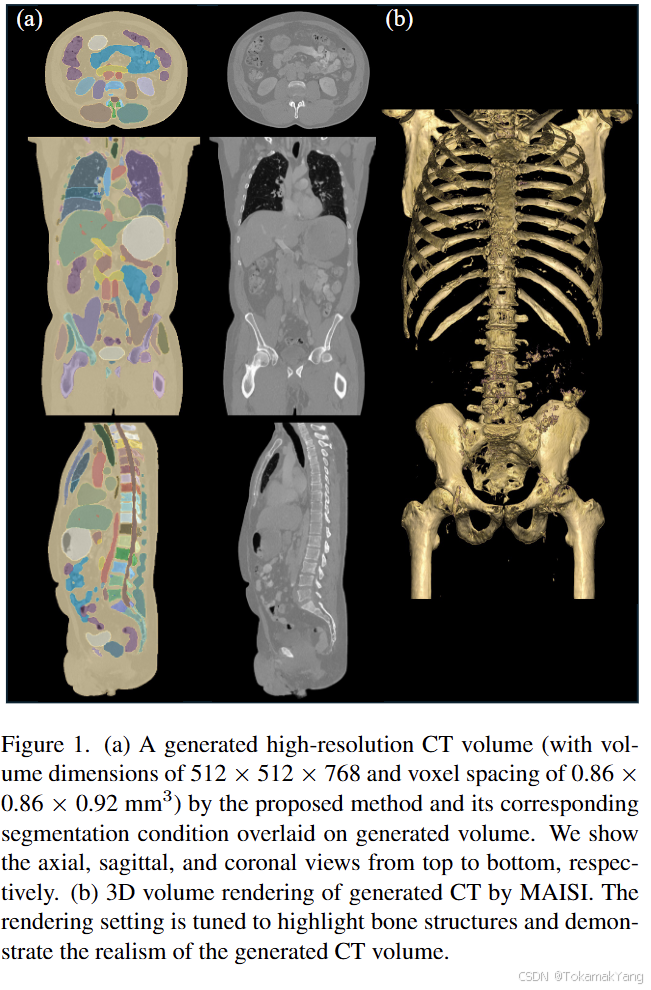

MAISI(Medical AI for Synthetic Imaging)是一种创新的基于扩散模型的方法,用于生成合成的3D计算机断层扫描(CT)图像,以应对上述挑战。MAISI利用基础体积压缩网络和潜在扩散模型,生成高分辨率CT图像,体积尺寸灵活,体素间距可调。通过引入ControlNet,MAISI能够处理包括127个解剖结构的器官分割图作为额外条件,生成带有准确标注的合成图像,适用于各种下游任务。

图 4 显示了三例异常病例的定性评估,可以看出 MAISI 在正常器官和异常肿瘤区域都能产生良好的 CT 生成质量,如每个子图的方框所示。我们的结果表明 MAISI 能以高保真度有效地描绘异常组织边界,证明了其在医学成像中基于分割掩模条件捕捉复杂细节方面的稳健性,MAISI 有可能有效地增强生成的 CT 图像的多样性和真实性用于数据增强目的。